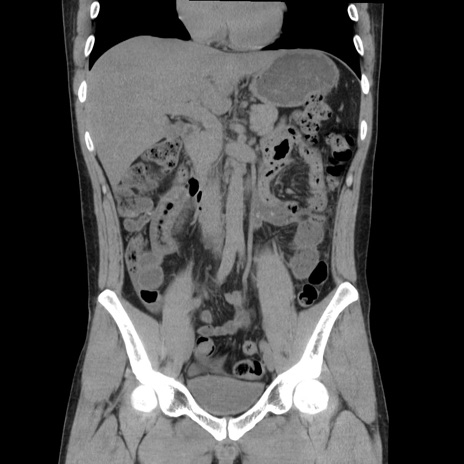

症例36(冠状断像)

【症例】20歳代 男性

【主訴】心窩部痛

【現病歴】今朝より上腹部痛あり。一旦軽快していたが再度出現したため救急要請。昨日夕に白身の魚を含む刺身を食べた。

【身体所見】BP 136/89mmHg、HR 74/min、BT 37.0℃、腹部:膨満、軟、心窩部に圧痛あり。反跳痛なし、筋性防御なし、腸雑音やや亢進あり。

【データ】WBC 17700、CRP 0.48